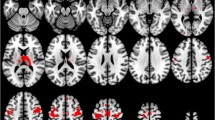

The inconsistency of volumetric results often seen in MR neuroimaging studies can be partially attributed to small sample sizes and variable data analysis approaches. Increased sample size through multi-scanner studies can tackle the former, but combining data across different scanner platforms and field-strengths may introduce a variability factor capable of masking subtle statistical differences. To investigate the sample size effect on regression analysis between depressive symptoms and grey matter volume (GMV) loss in Alzheimer’s disease (AD), a retrospective multi-scanner investigation was conducted. A cohort of 172 AD patients, with or without comorbid depressive symptoms, was studied. Patients were scanned with different imaging protocols in four different MRI scanners operating at either 1.5 T or 3.0 T. Acquired data were uniformly analyzed using the computational anatomy toolbox (CAT12) of the statistical parametric mapping (SPM12) software. Single- and multi-scanner regression analyses were applied to identify the anatomical pattern of correlation between GM loss and depression severity. A common anatomical pattern of correlation between GMV loss and increased depression severity, mostly involving sensorimotor areas, was identified in all patient subgroups imaged in different scanners. Analysis of the pooled multi-scanner data confirmed the above finding employing a more conservative statistical criterion. In the retrospective multi-scanner setting, a significant correlation was also exhibited for temporal and frontal areas. Increasing the sample size by retrospectively pooling multi-scanner data, irrespective of the acquisition platform and parameters employed, can facilitate the identification of anatomical areas with a strong correlation between GMV changes and depression symptoms in AD patients.